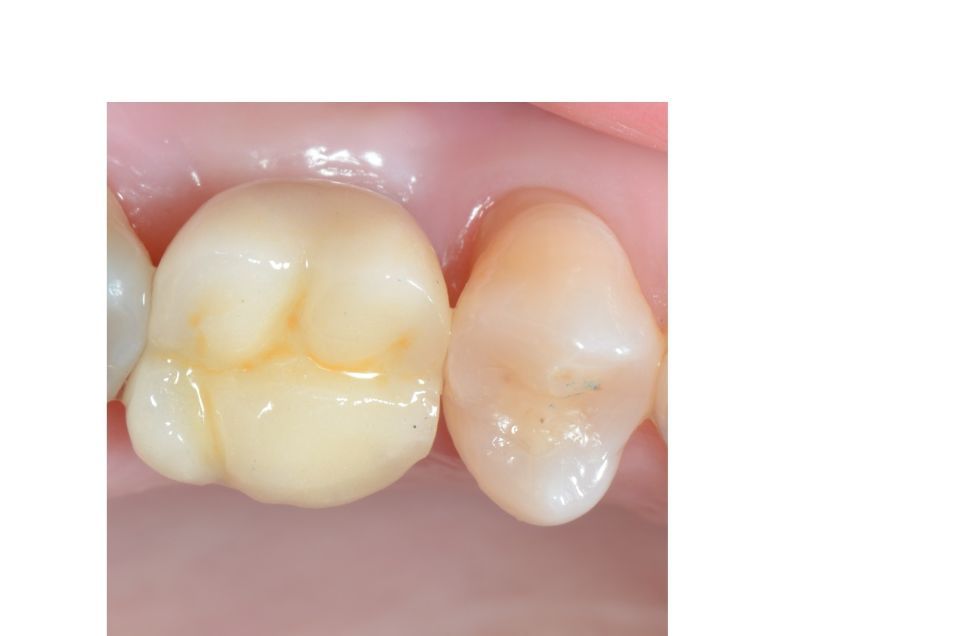

Rehabilitación con flujo digital

A través de las impresiones digitales en 3D realizamos rehabilitaciones protésicas mucho más perfectas y adaptadas desde el primer día, ya que la precisión del trabajo es mucho mayor, obteniendo resultados predecibles.

Se pueden realizar tanto en coronas sobre dientes naturales como sobre implantes, dando mayor comodidad y facilidad a los pacientes.